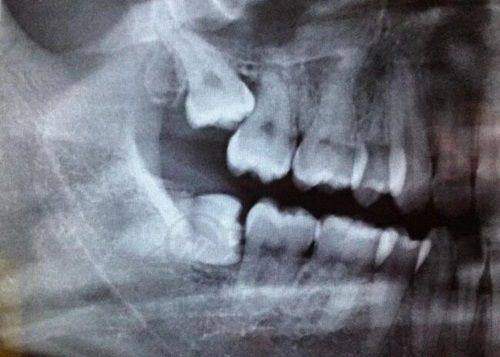

Twin Block矫正器(简称TB),是儿童青少年矫正“小下巴”“龅牙”的热门工具。它属于功能性矫治器,并非传统的固定托槽。其核心是通过上下颌垫斜面引导下颌前移,从而刺激骨骼改建。

生理性改建,更稳定:在6 - 12岁这个下颌骨生长高峰期,该矫正器通过持续温和的推力,使下颌骨自然延长,大大减少了成年后骨骼回缩的风险。同时,颞下颌关节会随下颌前移进行适应性改建,形成新的咬合平衡。

解决下巴后缩:如果孩子闭嘴时下唇包住上唇,侧面看下巴“消失”,就可能存在下巴后缩问题。Twin Block矫正器通过斜面引导下颌前伸,刺激髁突(下颌关节)生长,SNB角平均增加4.2°,有效解决下巴后缩。

矫正深覆合:当孩子上牙盖住下牙超过1/3,导致“露龈笑”时,就可以使用该矫正器。方法是分阶段磨低颌垫,让后牙自然萌出,重建咬合高度。

改善口呼吸:该矫正器具有联动设计,可加装唇挡或舌刺,训练唇肌闭合,扩大气道空间。[医院名称]的数据显示,70%的患者佩戴6个月后,夜间血氧饱和度提升5%。